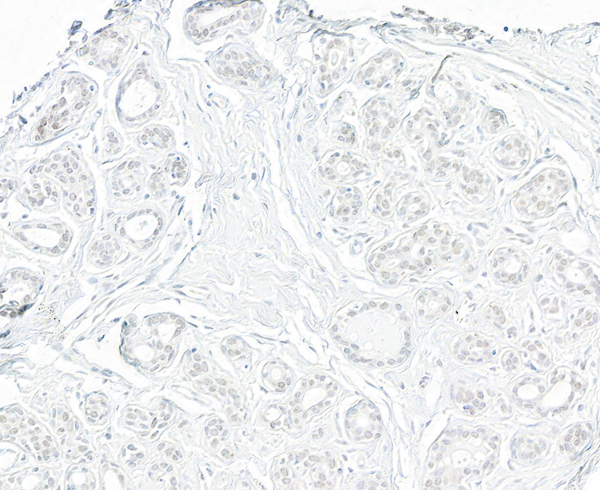

IHC (Immunohistochemistry)

(Detection of human TRIP1/SUG1 by immunohistochemistry. Sample: FFPE section of human breast carcinoma. Antibody: Affinity purified rabbit anti- TRIP1/SUG1 (AAA211143 lot 2) used at a dilution of 1:200 (1ug/ml). Detection: DAB)